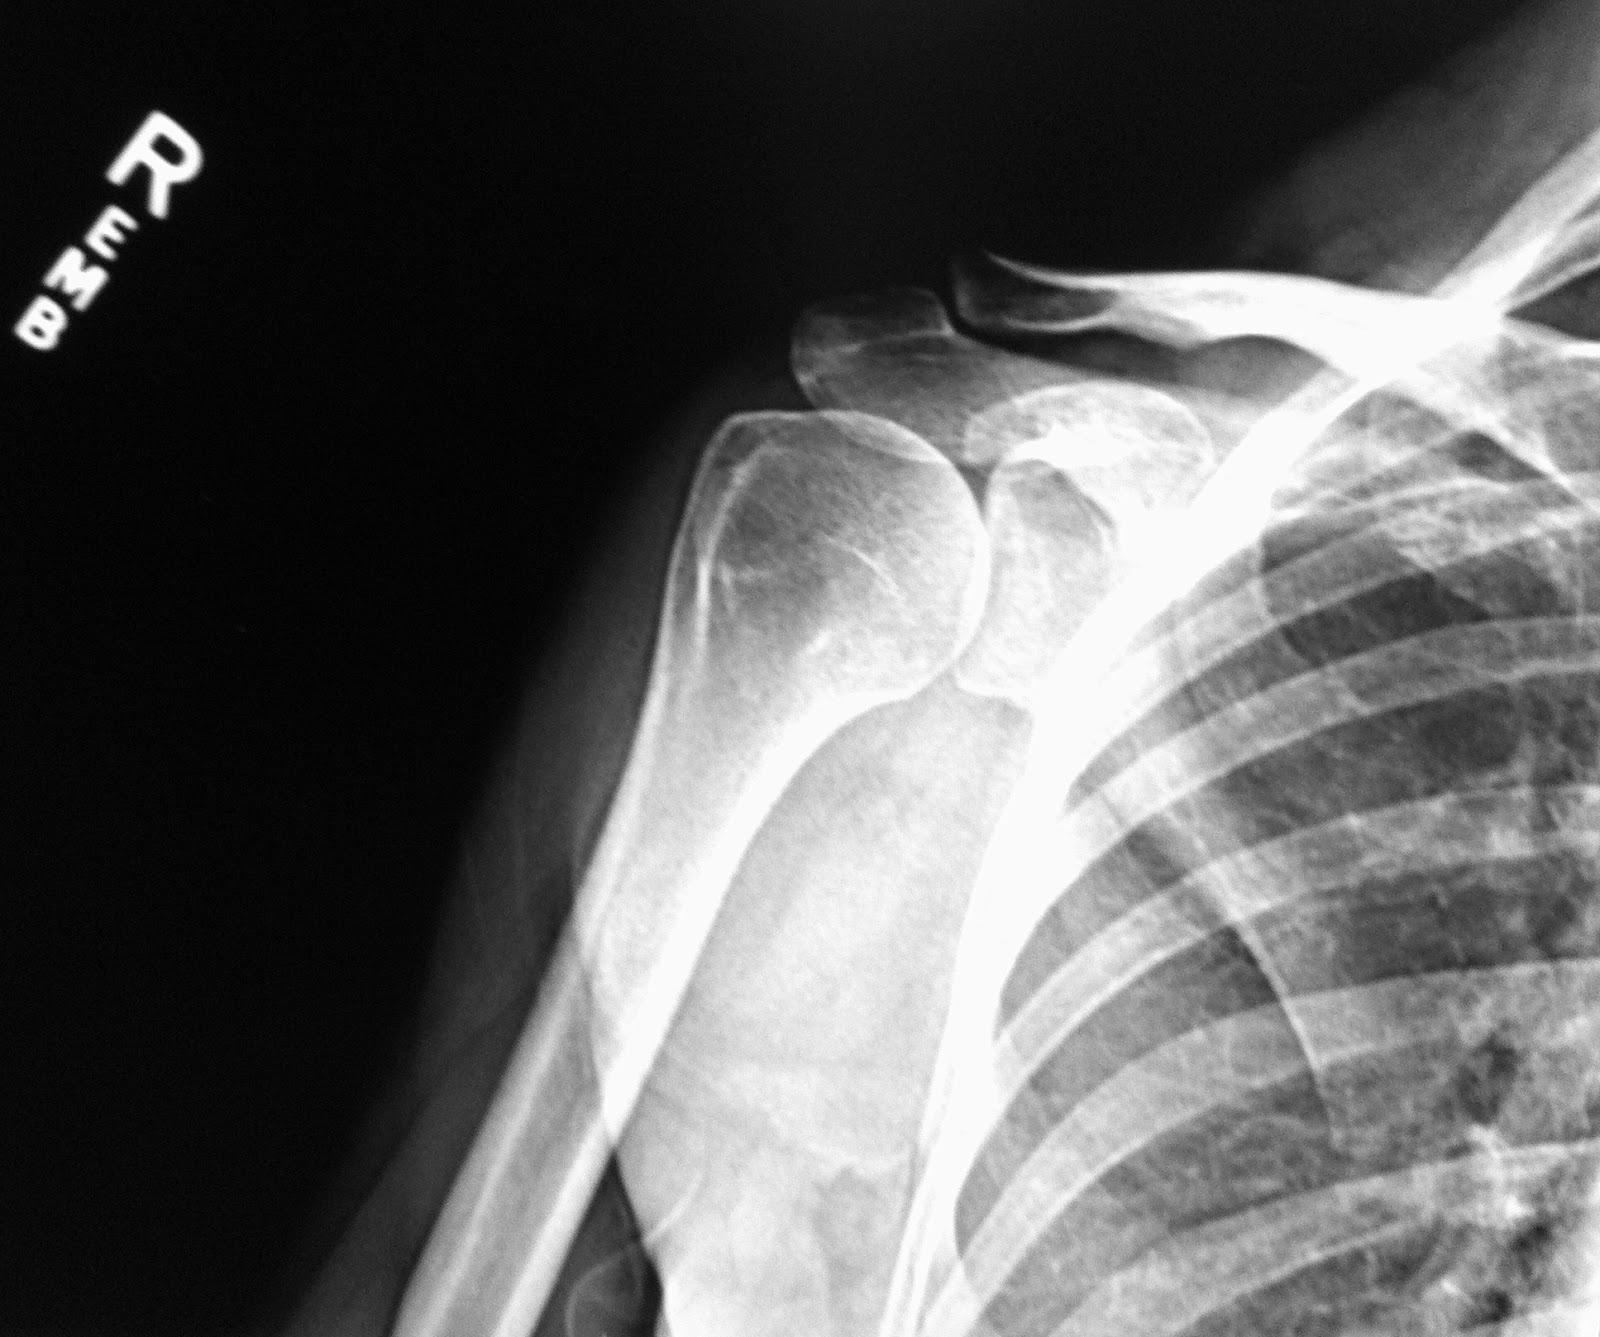

Anteroposterior (AP) Xray of the right shoulder at initial Adhesive Capsulitis X Ray The mri changes of adhesive capsulitis are most often observed at the rotator interval and the inferior glenohumeral ligament. A significant loss of passive range of. Adhesive capsulitis (also known as frozen shoulder) is a condition of the shoulder characterized by functional loss of both passive and active shoulder motion commonly. Adhesive capsulitis, also known as frozen shoulder, is most. Adhesive Capsulitis X Ray.